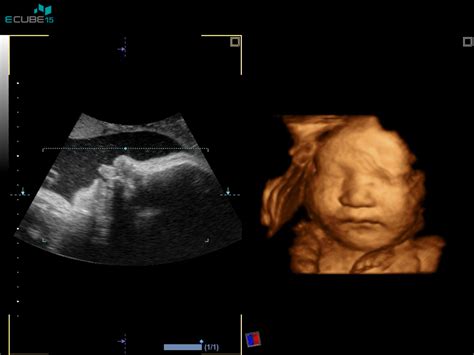

Nuhalna svetlina je prostor, ki se nahaja na zatilju ploda, med kožo in mehkimi tkivi, ki pokrivajo hrbtenico. V obdobju med 11. in 14. tednom nosečnosti je ta prostor napolnjen s tekočino. Pri večini zdravih plodov ta tekočina meri do 2,5 mm. Preiskava se zato opravlja v specifičnem časovnem okviru, ko je dolžina ploda (razdalja od temena do trtice) med 45 in 84 mm, kar običajno ustreza 11. do 14. tednu nosečnosti. Natančen časovni okvir je ključen, saj meritve zunaj tega obdobja niso zanesljive.

Izraz "nuhalna" v tem kontekstu pomeni "tilnična", kar se nanaša na zatilje ploda. Na ultrazvočni sliki je to območje videti svetlejše od okolice, od tod tudi izraz "svetlina". V tem zgodnjem obdobju nosečnosti se mezgovni sistem in ledvice ploda še razvijajo, kar lahko povzroči, da se tekočina ne odvaja pravilno in se nabira v območju zatilja, kjer je koža zelo raztegljiva. Ko se mezgovni sistem popolnoma razvije, se nuhalna svetlina običajno zmanjša ali izgine.

Natančno merjenje nuhalne svetline zahteva pravilen položaj ploda, zato lahko pregled traja različno dolgo. Med pregledom se izmeri srčna frekvenca ploda, njegova velikost od temena do trtice, premer glavice. Preveri se prisotnost nosne kosti, oceni se oblika glavice in možganskih struktur. Poiščejo se srce, želodček in mehur, ter se preveri, ali je trebušček v celoti prekrit s kožo. Preštejejo se dolge kosti na zgornjih in spodnjih udih ter pregleda hrbtenica.